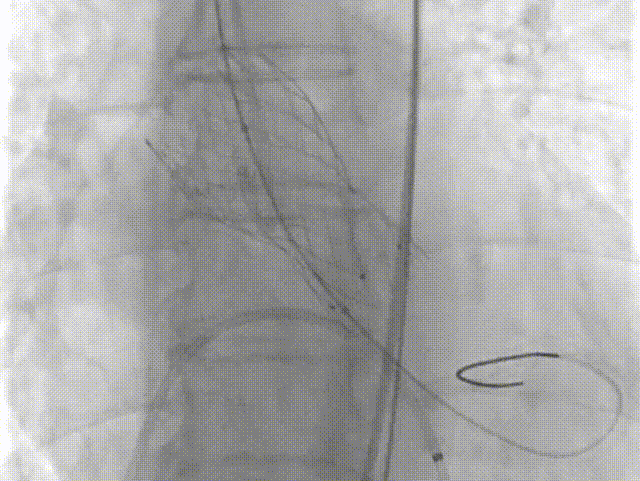

18球囊预扩张

瓣膜定位

瓣膜释放过程